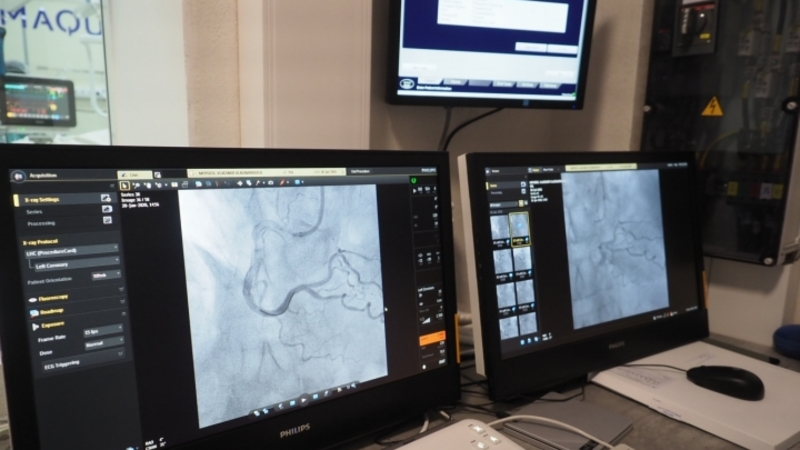

Только за текущий год в отделении рентгенохирургических методов диагностики и лечения Регионального сосудистого Центра  в Пятигорске выполнено 1320 процедур коронарографии. На сегодня это самый точный вариант детализации состояния у больных с ишемической болезнью сердца. Процедура представляет собой введение контрастного вещества в артерию с последующей рентгенологической визуализацией коронарных сосудов сердца, позволяет оценить их проходимость, определить тактику лечения при их стенозе. Более 700 коронарографий выполнялись вместе со стентированием сосудов различных локализаций. 93 пациента после проведения диагностической коронарографии были направлены на аортокоронарное шунтирование.